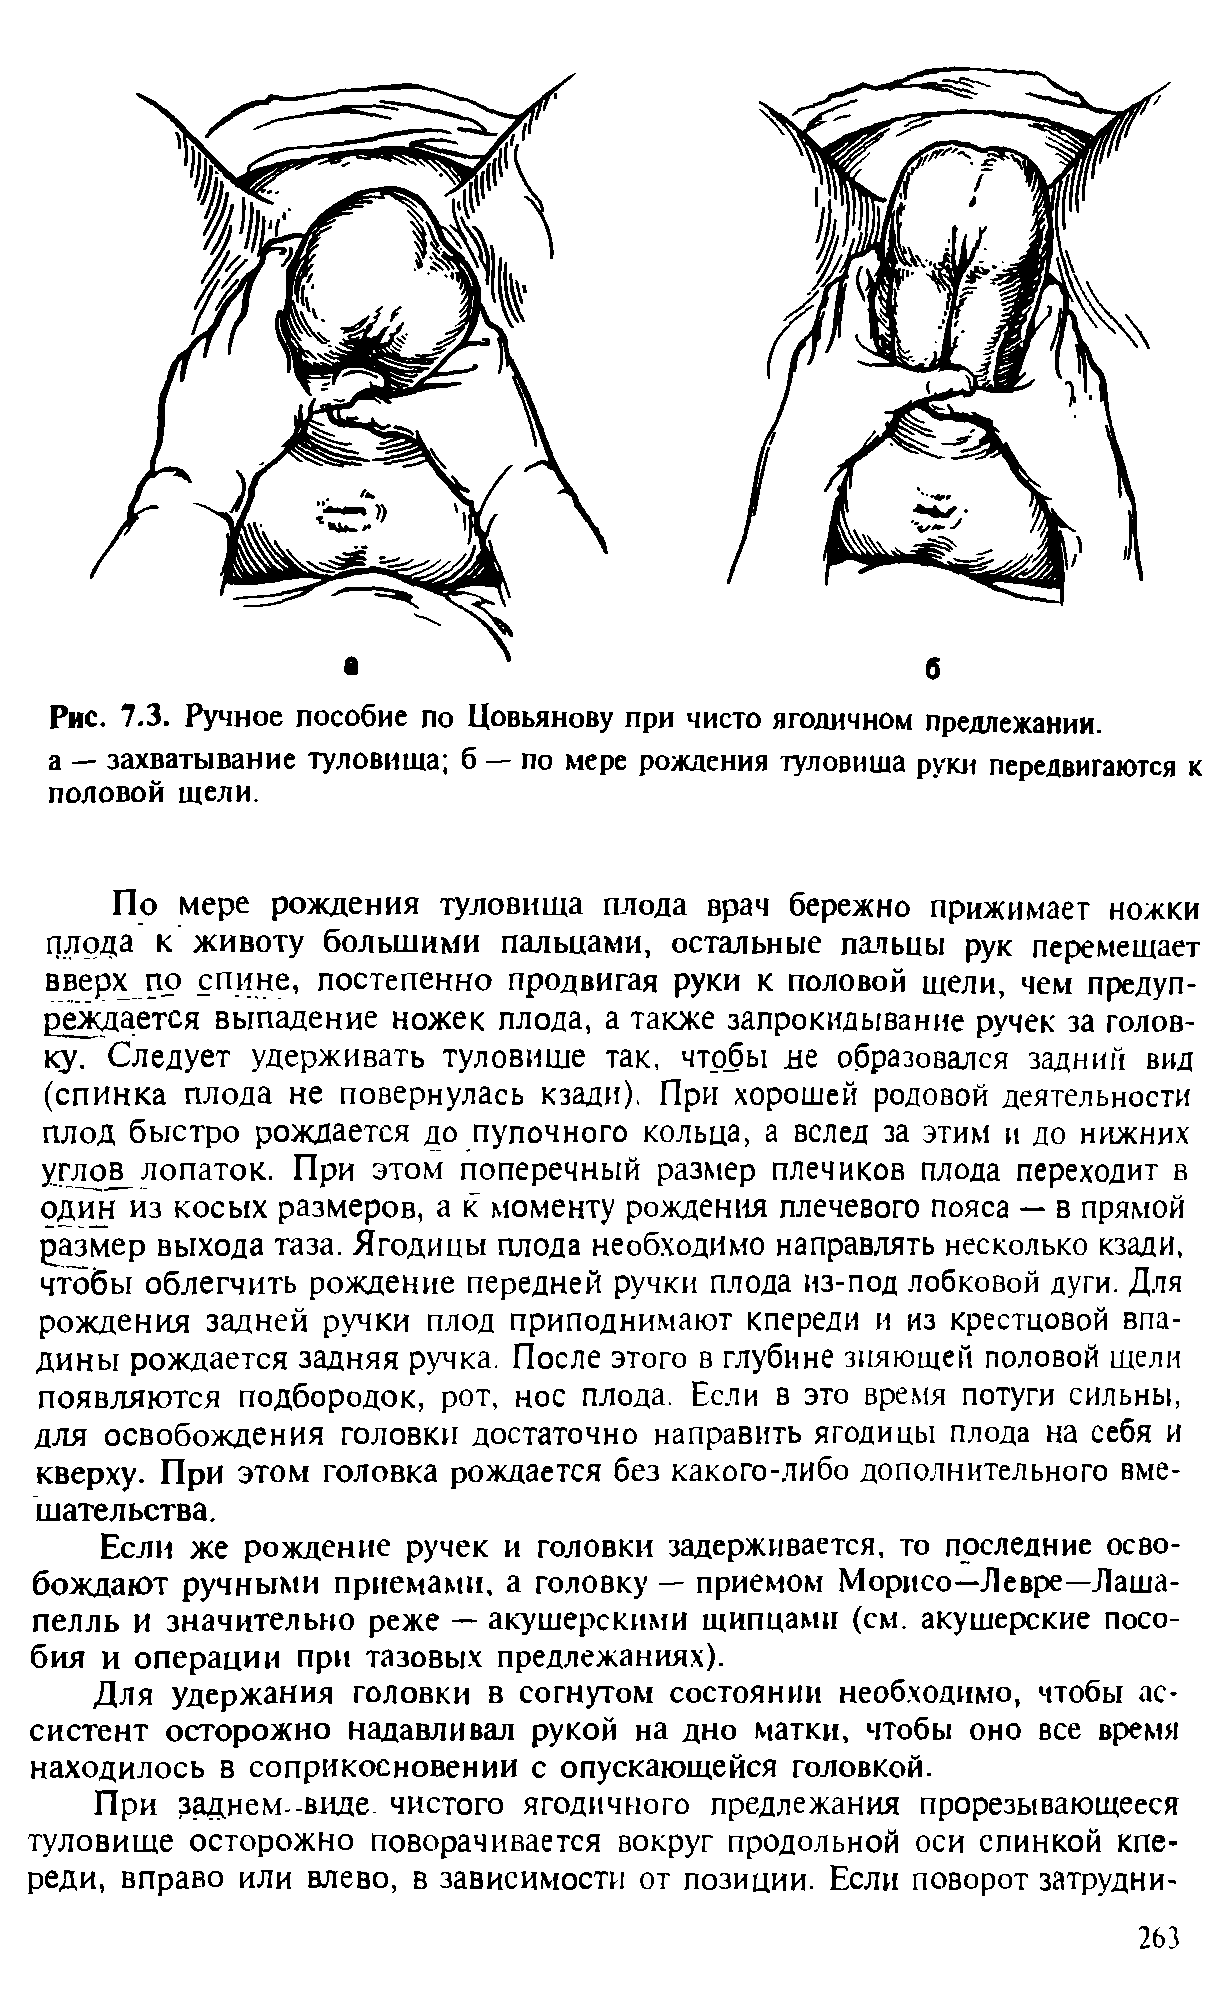

Метод Цовьянова при ягодичном предлежании

Пособие по Морисо Левре Лашапель